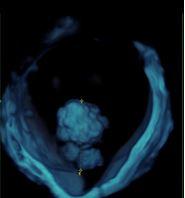

L’expertise dell’operatore, associato all’acquisizione da parte dell’Istituto di un’apparecchiatura di alto livello, dotata di software di ultima generazione anche con 3D e 4D, permettono di caratterizzare nei minimi dettagli l’eventuale presenza di patologia ovarica e di verificare l’eventuale disseminazione limitrofa agli organi circostanti. Questo da una parte dovrebbe permettere di evitare di misconoscere o sottovalutare alcune patologie ovariche potenzialmente evolutive in senso maligno e pertanto da indirizzare a trattamento chirurgico, e dall'altra di condurre un follow-up ecografico ad alcune patologie ovariche definite benigne secondo criteri standardizzati e ampiamente validati atti ad evitare una chirurgia non necessaria. Nel gruppo di lavoro IOTA infatti si è visto in questi anni che quasi l'80 percento delle masse ovariche operate risultavano benigne. E’noto che ogni procedura chirurgica è associata a possibili complicanze a breve come a lungo termine.